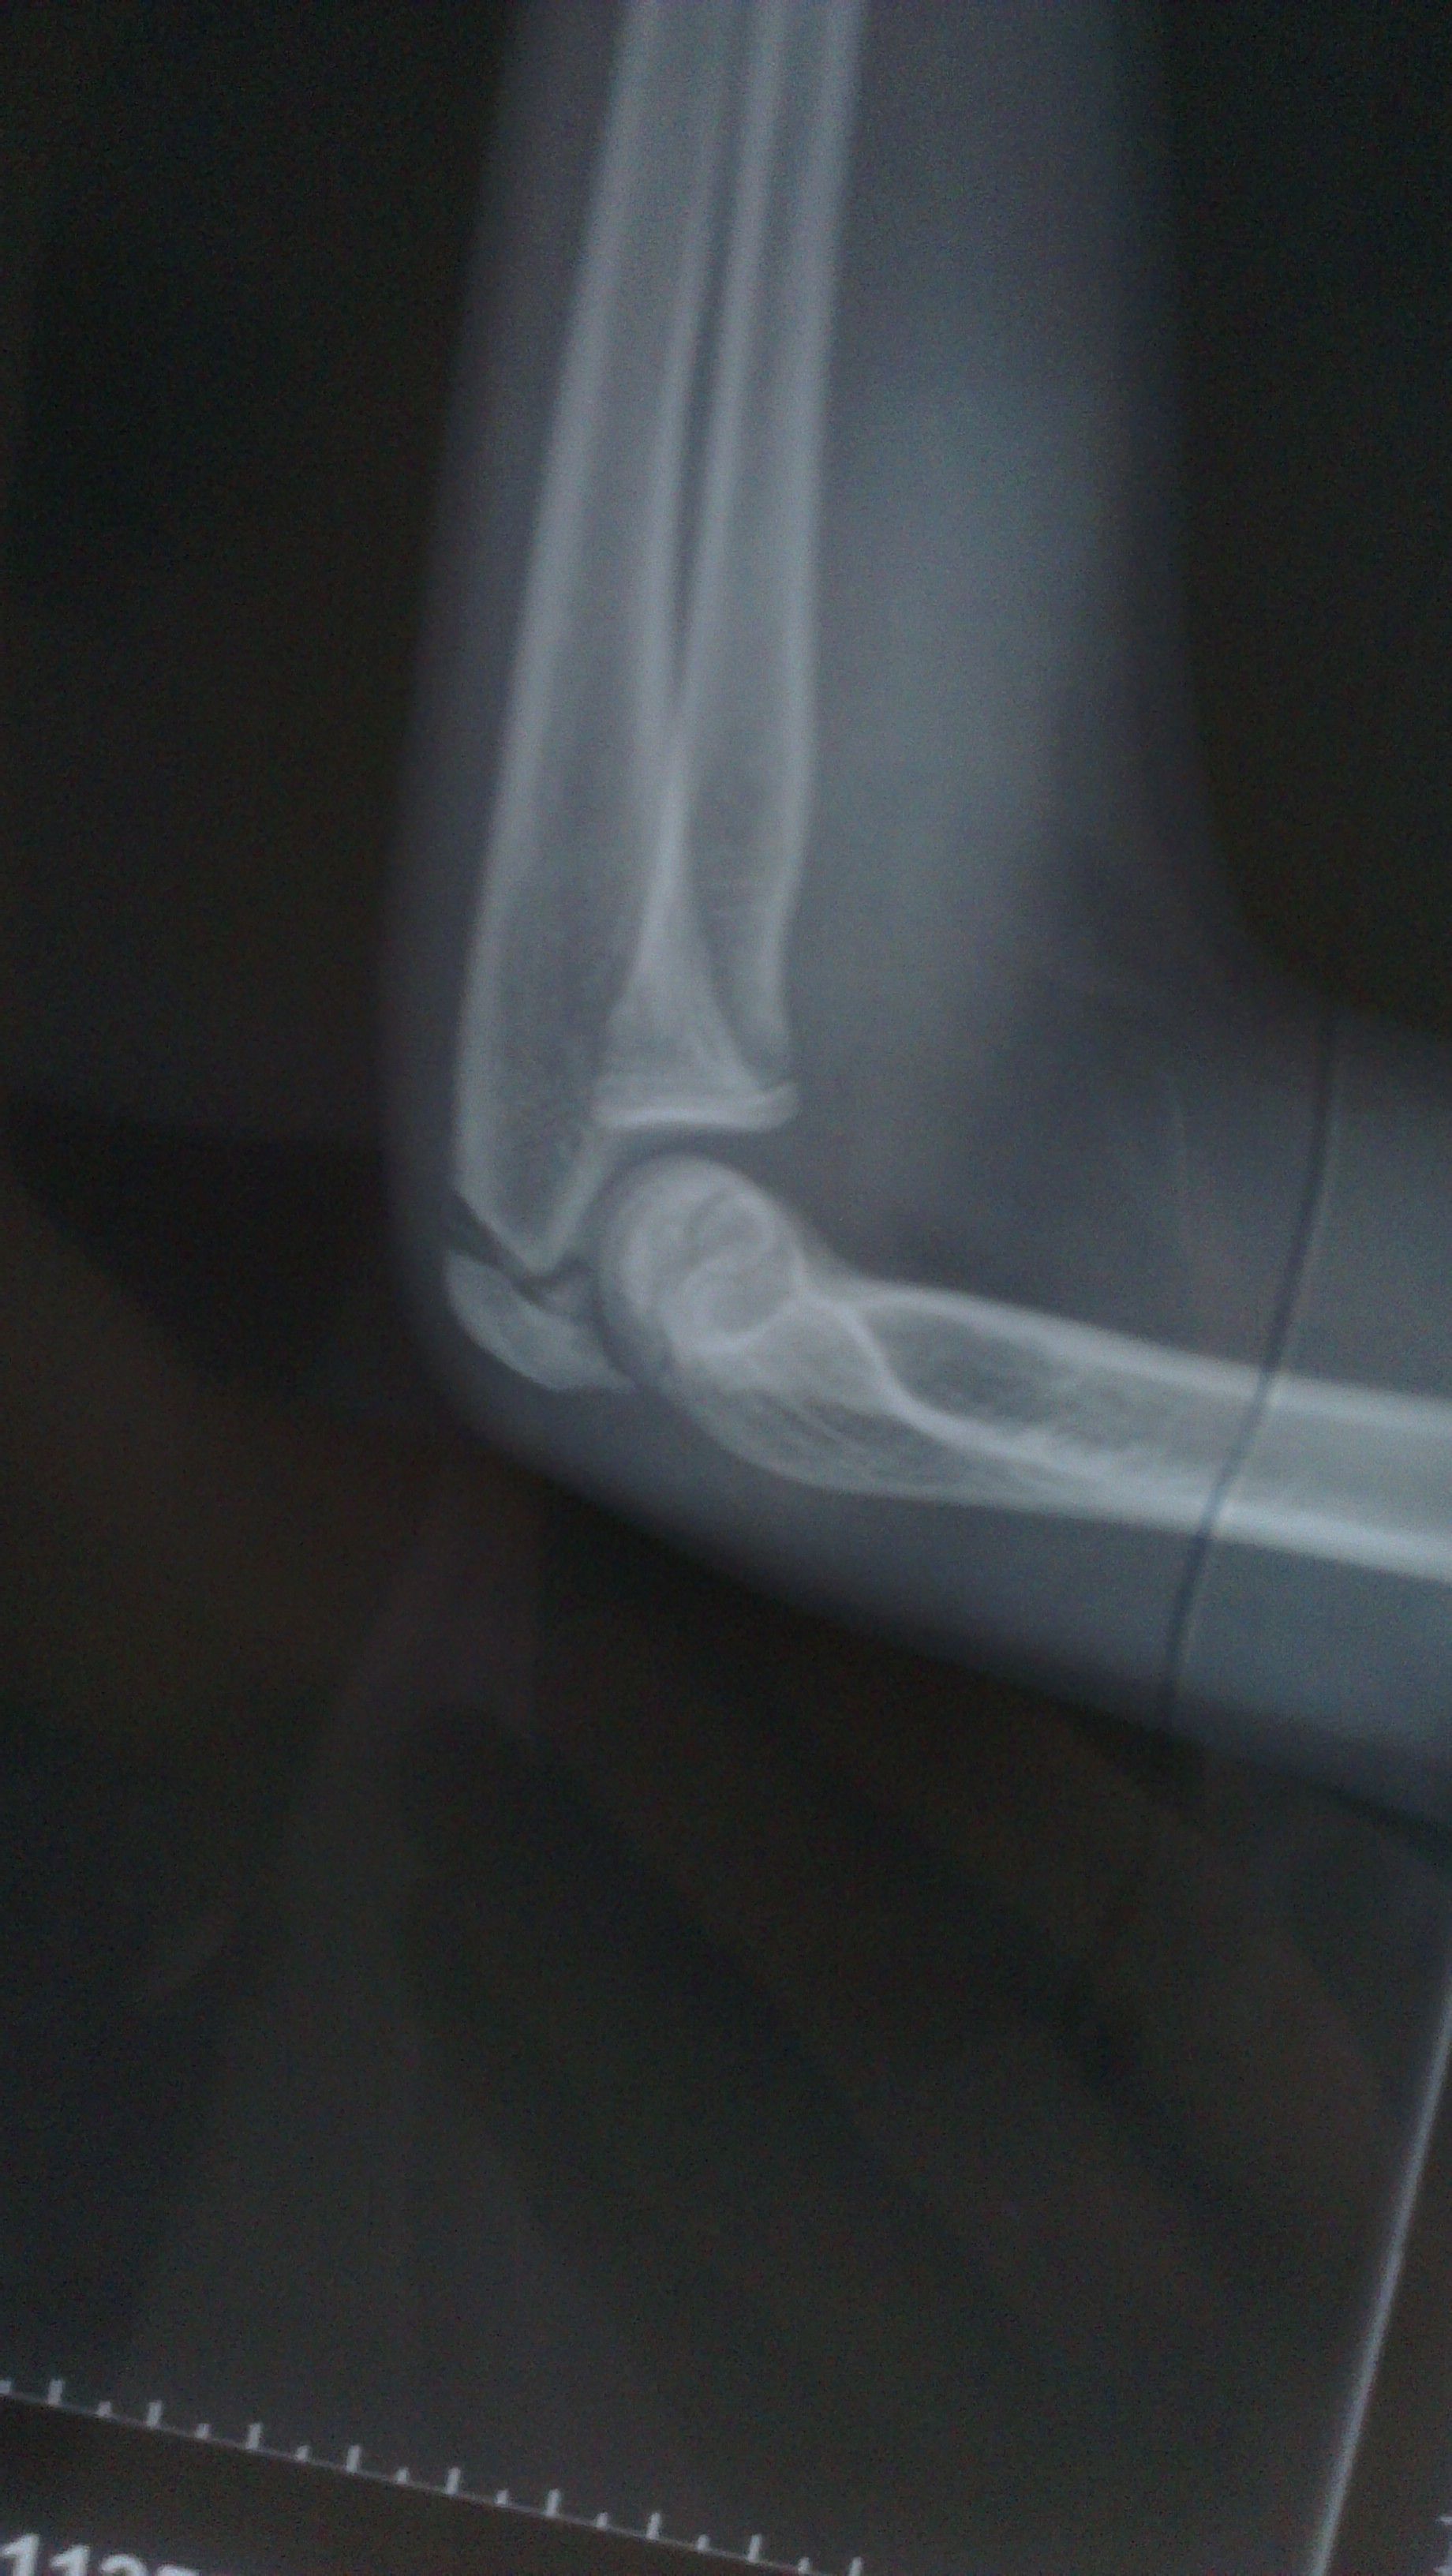

14岁小孩打篮球左肘关节负伤了 14岁小孩打篮球左肘关节负伤了,下面是片子,请专业医生诊断下:1,是什么问题?2,怎么治疗?有什么风险 点击展开 匿名用户 2014-06-27 12:49 为您推荐: 其他回答 你好,这个是要让医生给伤点药物的呢,还有就是要自己注意给宝宝好好的护理的呢,希望早日康复 可靠的悠闲80 2014-06-29 08:34 相关问题 四岁小孩肘关节骨折能保守治疗吗 你好!我小孩现14岁了他特喜欢打篮球 大家都说他可以进体校但是我又不知道哪里有啊我是重庆人 知不知道 有一个美国电影 一13岁小孩 在NBA 和大人们打篮球 这电影叫什么呀?